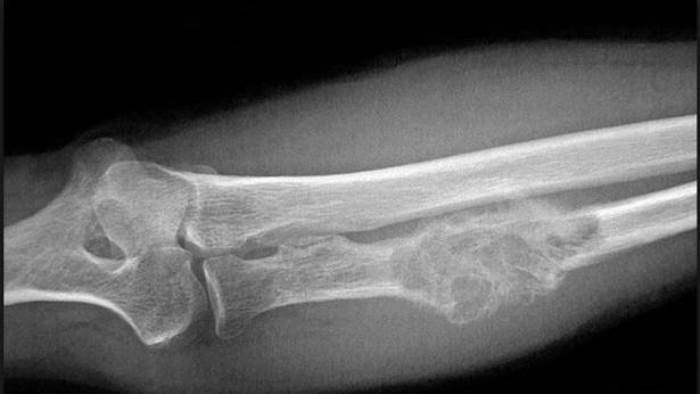

وكالات - الاقتصادي - بات السرطان في يومنا هذا من أشرس أنواع الأمراض الخطيرة والتي تنتشر كثيراً بين الناس. كذلك، إن خطورة هذا المرض تختلف بحسب نوعه ومكان نمو الورم.

ويعتبر سرطان العظام من أخطر الأنواع، لأنه يفتك بالجسم بشكل كبير.

من هذا المنطلق، قررنا أن نعرض عليكم عوارض هذا المرض الخبيث:

- آلام العظام أو المفاصل: قد يكون هذا الألم أكثر حدة في الليل أو عند المشي. ومع مرور الوقت يصبح الألم مستمراً.

-ظهور كتلة أو ورم على العظام: في هذه الحالة قد لا يشعر المرء بالألم.

-تغييرات في وظيفة المنطقة المتضررة.

-تكسّر العظام من دون معرفة السبب.